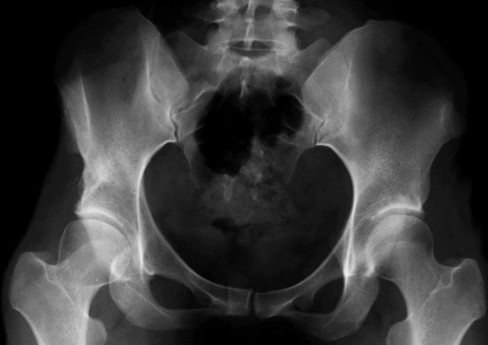

Alcuni mesi dopo, oltre ai disturbi della vascolarizzazione della testa femorale dx, si rende evidente un tetto inclinato o sfuggente. Di fronte al rischio di una perdita del risultato viene eseguita una tetto plastica. Si esegue una osteotomia del tetto che viene abbassato e reso orizzontale .

Il vuoto generato dalla correzione viene colmato con un cuneo di osso bovino. All’epoca non esisteva la banca dell'osso umano